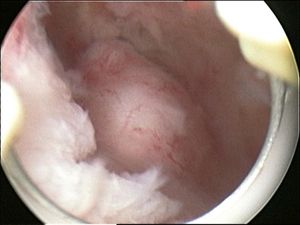

A relatively large submucosal leiomyoma; it fills out the major part of the endometrial cavity